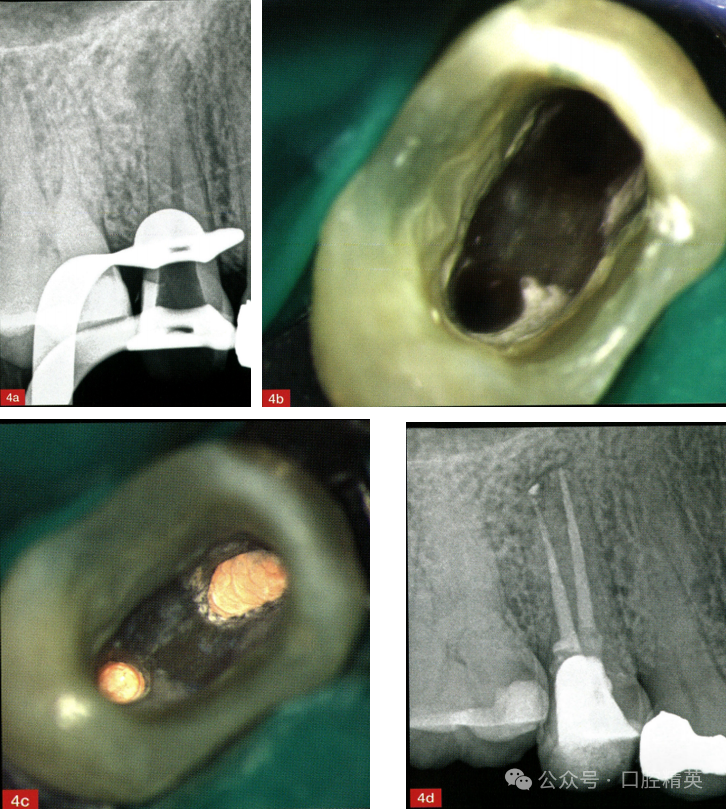

转诊患者,女性,58岁。影像学检查发现,右上第二前磨牙颊侧根管中上段可见分离器械(图1)。治疗计划是取出分离器械并完成根管再治疗(图2~图4)。

图1术前X线片显示颊侧根管内存在分离器械,腭侧根管充填不全。

图2超声器械去除不良修复体。

图3a,b修整开髓洞口,暴露分离器械上端(a),插入恰当的针头和胶水以固定并取出器械。

27号冲洗针头(BD MicrolanceTM 3针头27G×3/4"-0.4mm×19mm)和氰基丙烯酸酯胶水配合可取出分离器械,然后对患牙进行根管预备、消毒和充填,最后复合树脂直接修复。在本病例中,与其他分离器械取出技术相比,联合使用冲洗针头和氰基丙烯酸酯胶水是一种经济有效的处理方法。